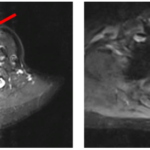

Ca lâm sàng: Điều trị thành công bệnh nhân ung thư tuyến giáp đã di căn xương cột sống sau 16 năm tại Trung tâm Y học hạt nhân và Ung bướu

GS.TS. Mai Trọng Khoa, PGS.TS. Phạm Cẩm Phương, Ths Lê Quang Hiển, BS. Vũ Thị Huyền Trung tâm Y học hạt...